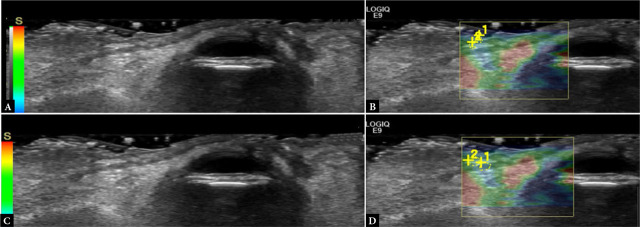

Methods: This is a prospective case-control study. Patients were recruited from the Oculoplastic Service of the Department of Ophthalmology at the University Hospital of Heraklion, Crete, Greece. The diagnosis of floppy eyelid syndrome was based on the eversion of the upper eyelid upon unassisted digital traction. Cataract surgery candidates without floppy eyelid syndrome were consecutively recruited as controls. Patients with a history of previous eyelid pathology or surgery were excluded. Ultrasound examination was performed using high-frequency linear probes (GE E9) for B-mode imaging and shear wave and strain elastography. Upper airway measurements included tongue thickness and upper airway length. Clinical and demographic findings were recorded.

Results: Twenty-eight patients were included (14 with floppy eyelid syndrome, 14 controls). Orbicularis muscle elasticity in kPa was significantly higher in the floppy eyelid syndrome group, compared with controls (independent samples t-test score 2.64, p = 0.04). Tongue thickness and upper airway length were also significantly correlated with several eyelid B-mode and elastography parameters in patients with floppy eyelid syndrome, including subcutaneous fat and orbicularis muscle thickness and elasticity.